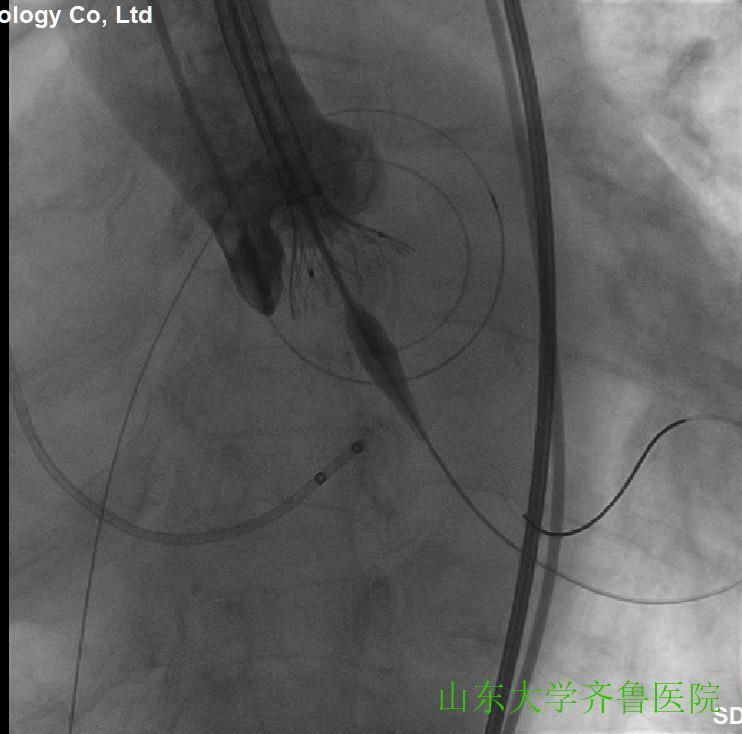

在手术室护士长翟永华及其护理团队、麻醉科吴剑波主任医师和杨绍忠主治医师的大力支持下,由心血管外科谷兴华主任医师、急诊心内科李传保主任医师、心内科安贵鹏副主任医师、心血管外科孙厚荣副主任医师及刘凯副主任医师、心脏超声室刘艳副主任医师和曹媛主治医师、放射科邵汉宏技师等在医院复合(Hybrid)手术室行一站式经导管主动脉瓣置换术(TAVR)+经皮二尖瓣球囊扩张成形术(PBMV)。手术先常规经颈静脉于右心室放置临时起搏导线并放置经食道TEE探头,行主动脉根部造影,明确主动脉瓣环平面、主动脉瓣钙化及返流情况(图1),导丝跨瓣入左心室并更换猪尾导管,测主动脉瓣跨瓣压差为76mmHg。选用24mm的擎源二尖瓣扩张球囊扩张2次,二尖瓣口面积由0.78?扩大至1.43?,并且二尖瓣无返流(图2)。选用20mmNuMed球囊,临时起搏心率180次/分,扩张狭窄的主动脉瓣(图3),应用26mmVenusA主动脉瓣介入瓣膜,准确定位、释放,造影、多体位透视及术中TTE显示介入主动脉瓣膜形态满意、无瓣周分流(图4-6)。术后即刻主动脉瓣最大跨瓣压差将至2mmHg。手术顺利,手术用时1小时40分钟,术后患者安返心脏外科监护病房。

图4选用26mmVenusA主动脉瓣介入瓣膜,定位,缓慢释放

图5临时起搏心率140次/分,缓慢释放介入瓣膜

图6释放介入瓣膜,形态、位置满意,造影时无瓣周分流